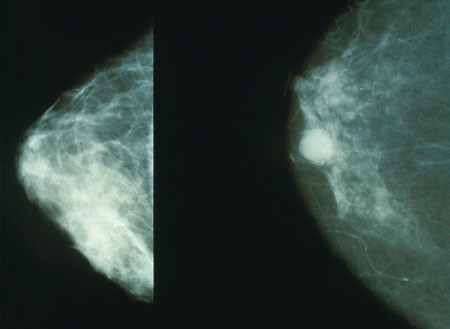

Unos científicos británicos han desarrollado un análisis de sangre para el diagnóstico precoz del cáncer de mama. Al parecer, este método sería más preciso que las tradicionales mamografías. Los científicos corresponden al Cancer Research UK, el Imperial College de Londres y la Universidad de Leicester, en Reino Unido.